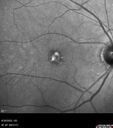

Most viewed - Collapsed Vitelliform Pattern Dystrophy

74 year old female: Seeing "Diamonds in central vision" when first waking up OU. Duration of Problem: about 6 weeks. Location: central vision. Modifying Factors: Lasts just a few minutes. Medical Hx: Cancer (Breast). Surgical Hx: Lumpectomy. Appendectomy. nose surgery. Systemic Meds: Ibrance. Faslodex. Zomita. Vitamin D3. VA OD: Dsc20/40+2 VA OS: Dsc20/50+1 IOP: TP: OD:18 OS:21

Pattern Dystrophy with Collapsed Vitelliform122 views74 year old female with vision loss in eye with collapsed vitelliform lesion.